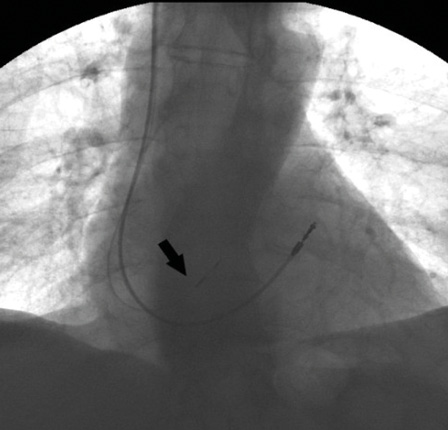

Рис. 3. Рентгенограмма после имплантации. Отражено два электрода: прежний, установленный в выходном тракте правого желудочка, и новый, имплантированный в область пучка Гиса (указан стрелкой)

Учитывая наличие у пациента постоянной формы ФП, артифициальной атриовентрикулярной блокады 3-й степени, постоянную электрокардиостимуляцию, а также клинические жалобы, пациенту показано оперативное лечение в виде замены ЭКС и имплантации электрода в область пучка Гиса. Отметим, что изобретение электрода с активной фиксацией Medtronic SelectSecure 3830 и системы доставки Medtronic SelectSite C304 позволило сделать методику более рутинной. В первую очередь нами был осуществлен доступ в правой бедренной вене по Сельдингеру и установлен интродьюсер. Затем проведено картирование кольца трикуспидального клапана под флюороскопическим контролем. Мы использовали электрофизиологический катетер для картирования с целью точного определения местоположения проводящей системы. Катетером выполняли поиск электрограммы пучка Гиса, что было критерием для фиксации спирали электрода в эту область. Изображение с локализацией пучка Гиса дублировалось на дополнительный монитор. Для поиска пучка Гиса применялся также метод униполярного картирования. Вторым этапом выполняли доступ к ЭКС, тестирование прежних электродов и венозный доступ (головная, подключичная или подмышечная вена) (рис. 2). Система доставки Medtronic SelectSite C304 предварительно моделировалась в теплом физиологическом растворе с целью обеспечения септального изгиба для позиционирования электрода в область перегородки. Система доставки заводилась в сердце по проводнику к кольцу трикуспидального клапана. Доставка позиционировалась в верхней части кольца клапана, вблизи области пучка Гиса. Контрастирование полостей сердца не проводилось. Затем электрод продвигался к кончику доставки в монополярной конфигурации. Кончик доставки находился в непосредственном контакте с перегородкой. После того как было отмечено соотношение электрограмм предсердий и желудочков 1:2, доставку направили в сторону перегородки минимальным вращением против часовой стрелки. Для картирования и стимуляции следует использовать электрокардиограмму с 12 отведениями. Как только местоположение Гиса определено, доставку необходимо удерживать неподвижно левой рукой, а электрод медленно вращать по часовой стрелке 5 раз. Очень важный момент – количество попыток вкручивания электрода. В нашем случае электрод был позиционирован со второго раза. После этого доставку вытянули назад, а электрод осторожно протягивали вперед, пока в предсердии не сформировалась петля. Предпочтительно тестирование при длительности импульса 1 мс, чтобы обеспечить более низкий порог. У большинства пациентов порог стимуляции пучка Гиса составляет 2,0 В в 1 мс. В нашем случае порог стимуляции был 3,6 В при длительности импульса 1,5 мс, стимуляционный импеданс – 669 Ом. Как только приемлемый порог был достигнут, доставка была разрезана и удалена. Электроды коммутированы с ЭКС His – A, RV-RV (рис. 3). Вектор QRS идентичен нативному. Базовая частота была 60 имп/мин в биполярном режиме стимуляции (режим DDD(R), атриовентрикулярная задержка 100 мс). Длительность операции составила 140 минут, длительность радиационного облучения – 5 минут. Эффективная доза облучения – 0,025 мЗв [7].